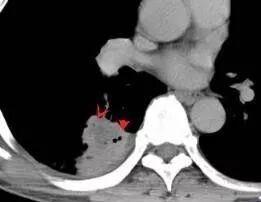

DWI值对鉴别脑脓肿与囊性脑转移瘤有重要意义。包膜期脑脓肿其内容物主要为炎症细胞、微生物及蛋白质,其黏稠度相对较高,水分子弥散受到限制,DWI表现为均匀高信号。转移瘤囊变区主要以浆液性坏死物为主,其黏稠度相对较低,水分子扩散速度相对较快,DWI表现为低信号

脑脓肿和囊性脑转移瘤的鉴别点就是粘液(结合水)浆液(自由水)的鉴别

下图是例举其他病例: